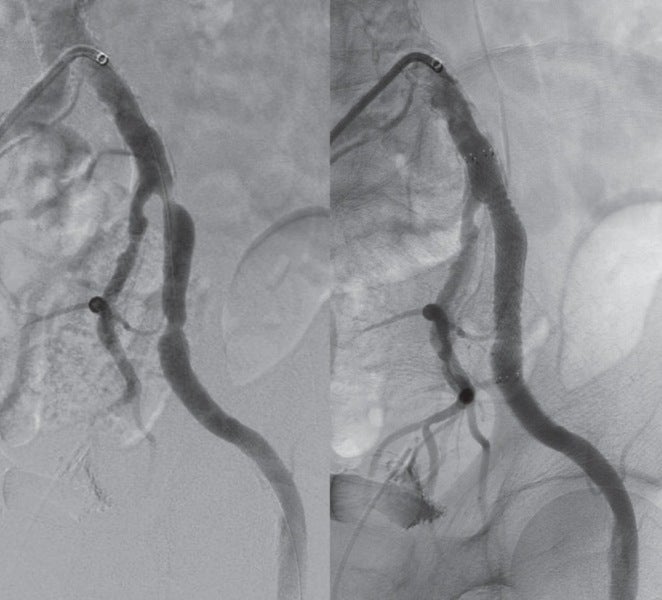

比較的若年のSFA-CTO症例であったが、患者は低侵襲であるEVTを希望された。 仕事が多忙とのことであり、何度もEVTを行うのは難しい状況のため、できるだけバイアバーン® ステントグラフト留置によって長期開存が得られるよう十分な内腔の確保、healthy landingを念頭に、将来的に万一閉塞した場合に備えて側副血行路の温存を考えた。(図1、2)

術前のCTAでは左EIAに高度狭窄を認めたため、対側CFAアプローチとした。腸骨動脈領域はびまん性高度石灰化を伴っていたが、大腿膝窩領域にはSFA遠位部にスポットな石灰化を認めるのみであった。CTOに対するワイヤリングに際して、当院では使用するデバイスの種類にかかわらず十分なデバイス拡張を得るためにIVUSガイドワイヤリングを行い、intraplaqueを通過するよう心がけている。ただし、本症例は心房細動の既往もあり血栓性病変である可能性も考えられたため、ガイドワイヤー通過後にIVUSでプラークの診断を行い、必要があれば末梢保護デバイスの使用を考慮することとした。

対側CFAより6 Fr 45 cm長のガイディングシースを挿入し山越えにて左EIA遠位部に進めた。この時点で圧波形は問題なかったため、手技を継続することとした。まず、5.5 Fr 100 cm長のガイディングカテーテルのバックアップ下、IVUSガイドに0.014 inchガイドワイヤー(先端荷重3 gポリマージャケットタイプ)を進めたところ、比較的容易にガイドワイヤー通過に成功した。IVUSでは全長にわたり intraplaqueを通過していたものの、血栓成分の多いプラークと考えられた。このため、5.5 FrのガイディングカテーテルをSFA遠位部に先進し、フィルターワイヤー(径 8 mm)を膝窩動脈に留置し遠位部保護を行った。続いて、5.5 Frガイディングカテーテルを用いて血栓吸引を行ったうえで、小径バルーン径 4.0 mm / 長 220 mmを使用し6 atmで前拡張した。(図3)この時点で造影にて末梢塞栓のないことを確認しフィルターワイヤーを回収、0.035 inchガイドワイヤーを用いて7 Fr 55 cm長のガイディングシースへ交換した。0.014 inchガイドワイヤー(先端荷重 1 g 親水性コートタイプ)を挿入後、SFA遠位よりバイアバーン® ステントグラフト径 7.0 mm / 長 150 mmを留置し、バルーン径 6.0 mm / 長 80 mmを用いてステントグラフト内のみ 18 atmで後拡張を行った。続いて、SFA近位部のlanding zoneをIVUSマーキングしたうえで、(図4)バイアバーン® ステントグラフト径 7.0 mm / 長 100 mmを追加留置した。先述のバルーン径 6.0 mm / 長 80 mmを用いて高圧拡張の後、近位部のみバルーン径 7.0 mm / 長 100 mmを使用し12 atmで後拡張を追加した。IVUSにてステントグラフトの拡張が良好かつmalpositionがないことを確認した。 最後に、EIAに対してベアメタルステント(BMS)径 10 mm / 長 60 mmを留置、後拡張を行って手技を終了した。(図5、6)